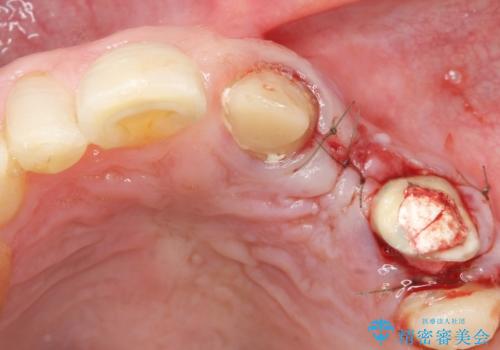

歯を牽引し健全歯質を歯肉縁上まで引き上げ、歯の保存を試みることにしました。

歯の牽引後、ブリッジの仮歯で保定しながら歯肉・骨の治癒を待ったのち、ブリッジによる補綴を行いました。

健全歯質を歯肉縁上に出すためにしっかり挺出させたことで歯根長が短くなりましたが、仮歯で十分に保定した結果動揺度Ⅰ程度となり、ブリッジの支台歯にすることが可能と判断しました。